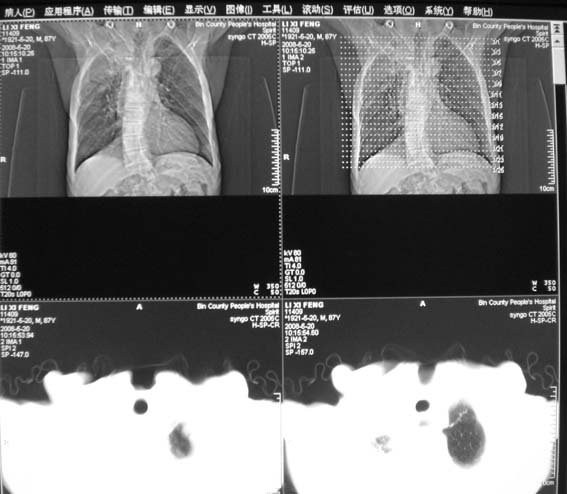

男,87岁,咳嗽、发烧、有黄痰,胸片示肺结核。

右肺上叶尖后段片状不规则致密影,密度欠均匀,相邻胸膜肥厚,纵隔内见多发肿大、钙化淋巴结,考虑为结核,部分坏死

右侧上叶结核,干酪性肺炎,慢支